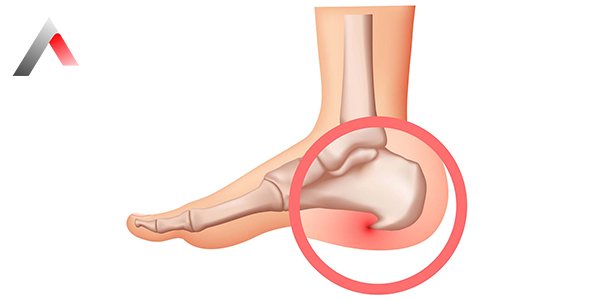

Topuk Dikeni Tedavisi

Topuk Dikeni Tedavisi Nasıl Yapılır?